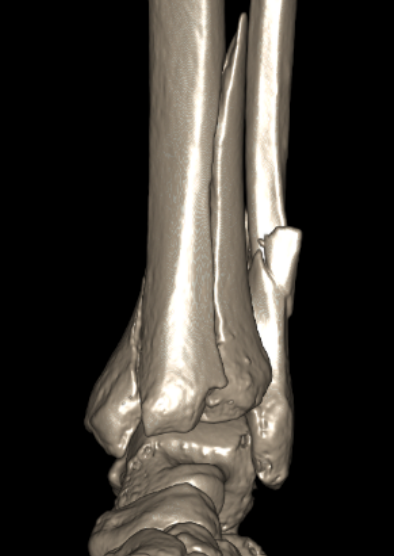

CT scan

Commonly 3 fracture configurations

- medial malleolus

- posterolateral fragment / Volkmann

- anterolateral fragment / Chaput